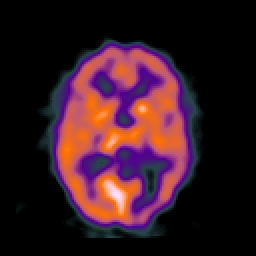

SPECT TC Study #6 -- Slice #29

[Home][Help][Clinical][Tour 1][Tour 2][Tour 3] Slice 29